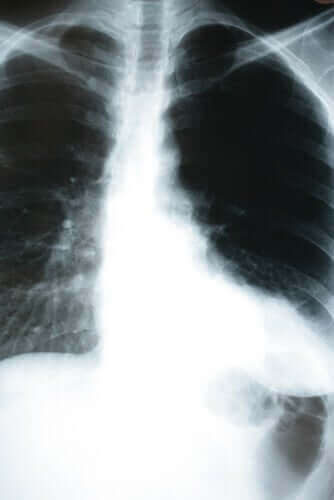

Oireettomassa keuhkokuumeessa käy kuitenkin päinvastoin. Useissa New Yorkin ja Brasilian sairaaloissa huomattiin, että monilla ihmisillä oli keuhkokuume, mutta he vaikuttivat voivan hyvin. Keuhkokuume havaittiin mittaamalla veren happipitoisuus tai ottamalla röntgenkuva rintakehästä.

Jos siis epäilet sinulla olevan koronavirus, suosittelemme, että annat lääkärin mitata veresi happisaturaation ja ottaa röntgenkuvan rintakehästä. Tämä on erityisen tärkeää silloin, kun olet ollut kosketuksissa tartunnan saaneen ihmisen kanssa tai jos kuulut riskiryhmään.